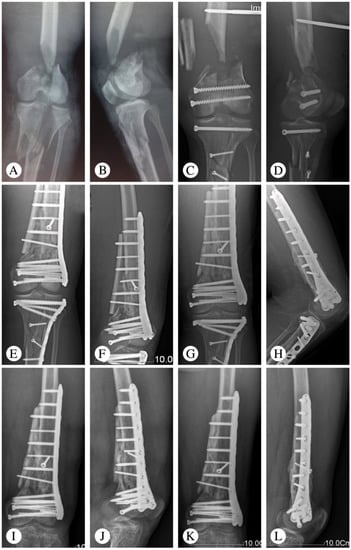

One patient had a deep infection five days after the operation and underwent a secondary surgery (implant removal and external fixation). There were two patients who had minor surgical complications, including one superficial wound infection and one partial wound dehiscence. After debridement and suturing, both patients’ complications were resolved. One patient with nonunion required bone grafting without hardware exchange. Post-traumatic arthritis was seen in one patient at the final follow-up, which was based on the radiologic assessment (Table 2). Typical cases are shown in Figure 1 (Patient 2), Figure 2 (Patient 5), and Figure 3 (Patient 10).

Figure 3. Representative images of Patient 10 (21-year-old male patient with a Gustilo IIIB fracture resulting from a traffic accident). (A,B) X-ray at admission. (C,D) X-ray after emergency operation. Limited internal fixation combined with external fixation was utilized. (E,F) X-ray 3 months after an interfixation operation. (G,H) Follow-up X-ray at 9 months. (I,J) Follow-up X-ray at 12 months. Removal of the tibial implant. (K,L) Follow-up X-ray at 69 months.